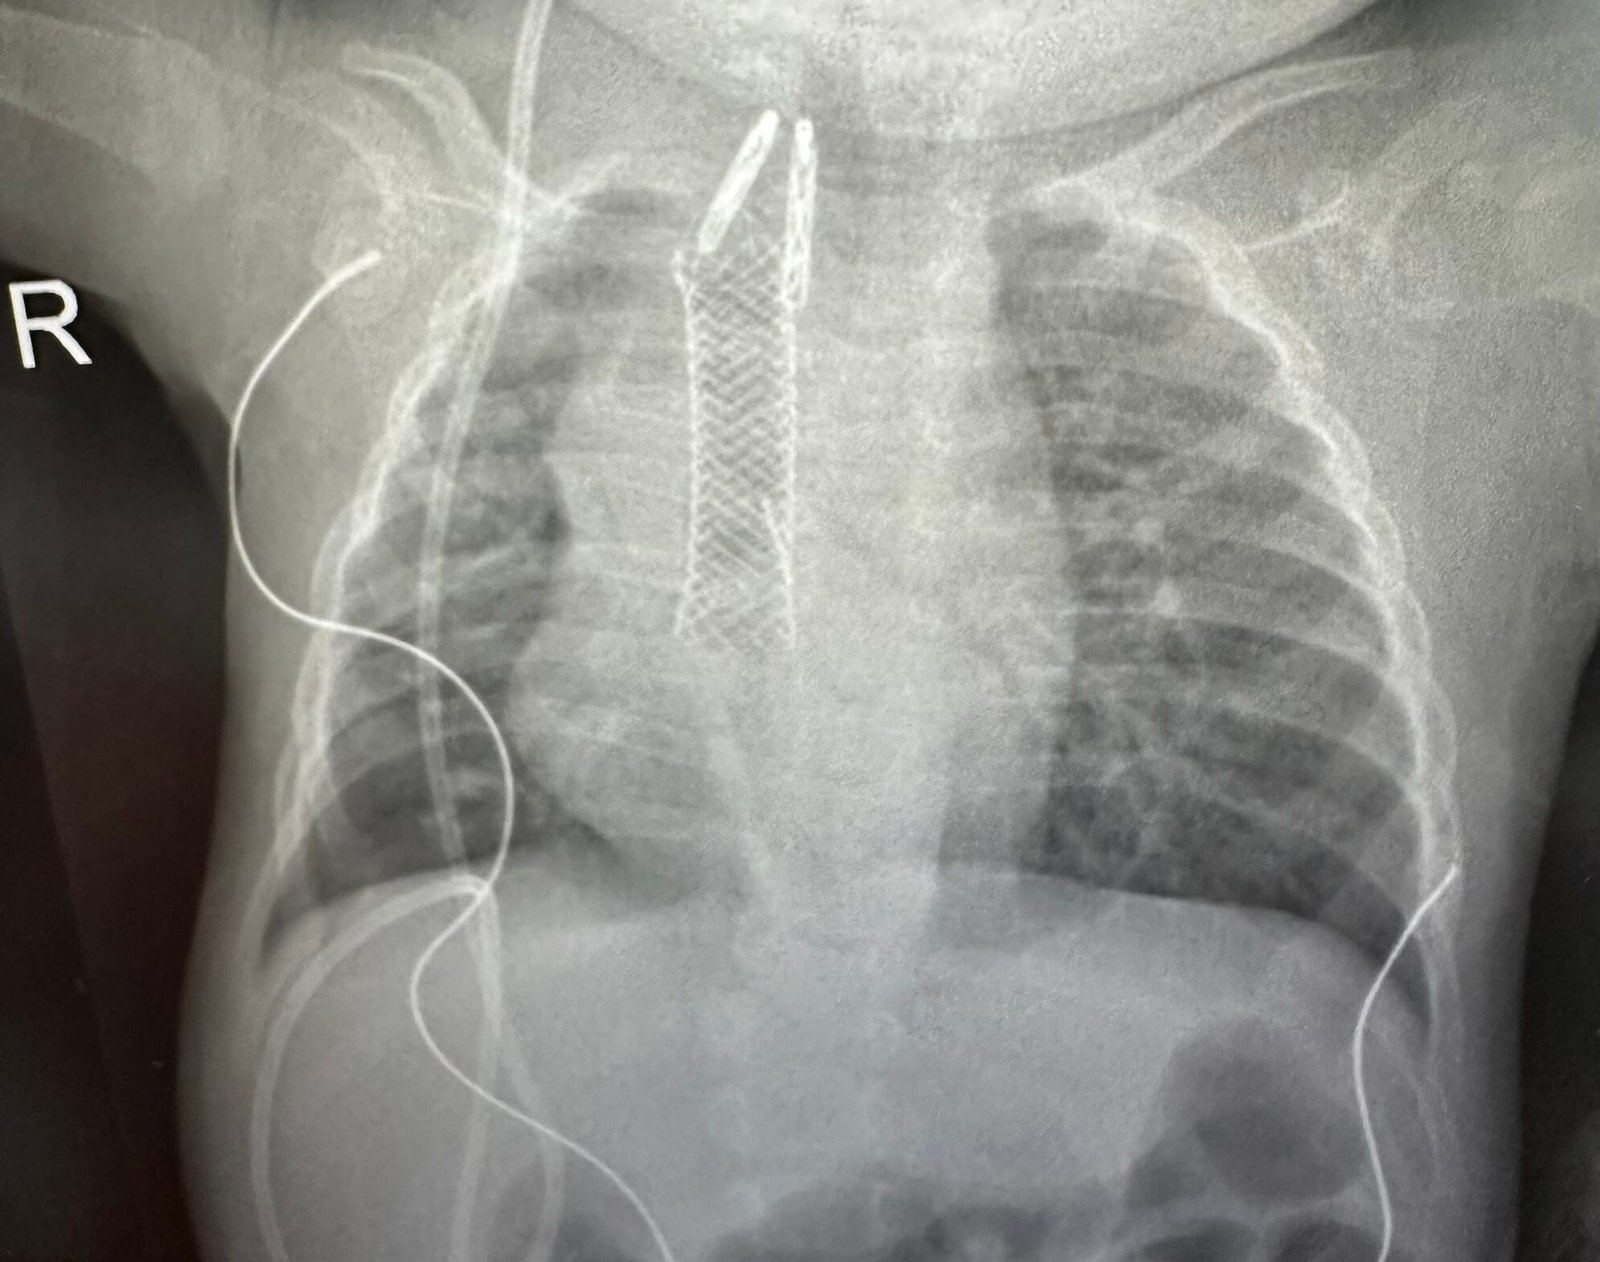

After several intense days in the hospital, we brought Imani home with a stent in her esophagus. It was meant to stay in place for nine weeks to keep her esophagus open. We were relieved to be back, but feeding her was anything but easy.

But a few months later, the signs returned. She struggled to swallow. She started refusing food again. We knew something was wrong. Back at the hospital, another scan showed her esophagus had narrowed again.

She was admitted and a second stent was placed. It was the only thing that had helped her before, and thankfully, it helped again. She started eating again, slowly but surely. Some days were easier than others. But she wanted to try and that meant everything.